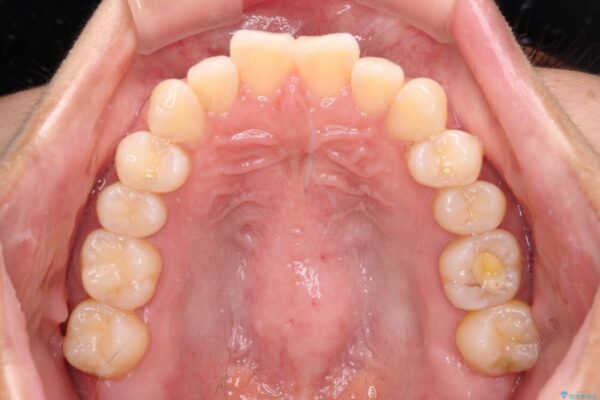

上顎前歯が捻れて前方に飛び出しており、下顎前歯もそれに沿うようにデコボコとなっていました。

IPR(歯と歯の間を削る処置)によりスペースを獲得して上下顎前歯のデコボコを改善し、飛び出している前歯が引っ込むように設定し、インビザラインにて矯正治療を行うこととしました。

治療後について

装着時間を守ってくださったので、予定通りの期間で終えることができました。インビザライン特有の、奥歯の咬み合わせの問題もなく、しっかりと歯列を改善することができました。

治療後

• 【モニター】前歯のデコボコをインビザラインで改善 治療後画像